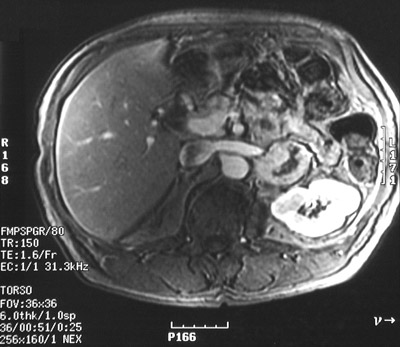

This abdominal T1 enhanced MRI scan shows a left adrenal pheochromocytoma with central necrosis.